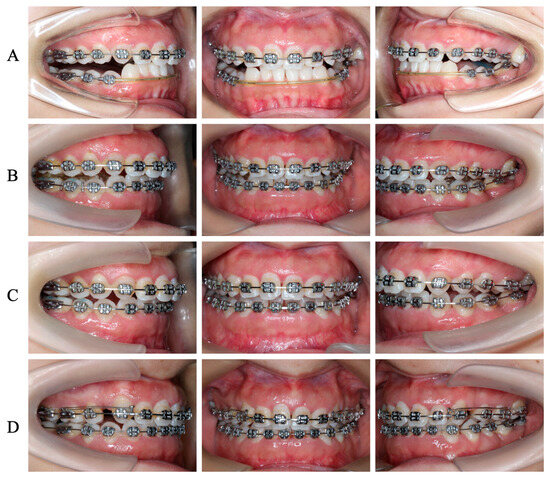

3.2. Orthodontic Treatment before PCRS

3.4. Postoperative Orthodontic Treatment and Maintenance

3.5. Periodontal Maintenance